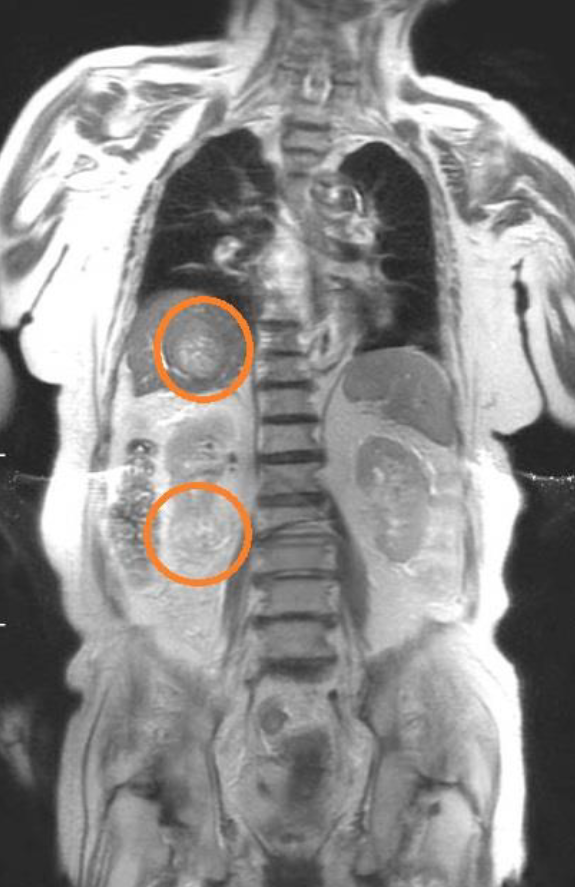

MRI の高性能化によって可能となった「全身のがん検査」です。「全身のがん検査」を行う PET と同じ様な画像を表示します。

【がん早期発見MRドック でわかる事】

肺癌、大腸癌、胃癌、膵臓癌、肝臓癌、胆嚢癌、胆管癌、乳癌、悪性リンパ腫、食道癌、 膀胱癌、腎臓癌など

A.頸部~骨盤部を撮影範囲とする様々な病気を発見できる撮影法で、早期発見に有効と考えます。

MRI検査の撮影法の1つである「拡散強調画像(DWI)」というもので撮影しています。「DWI」ではがんの細胞密度増加に伴う水分子の拡散制限を検出することができます。また他の撮影も実施しているので、がんやその他様々な病気の発見が期待できるため、自覚症状が出る前から定期的な検査をお勧めしています。